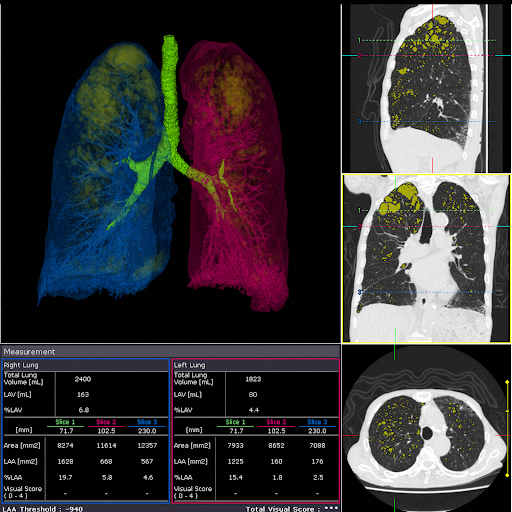

Анализ легочных объемов

Анализ объема легких происходит автоматически за счет количественного определения тканей в полях легких (области эмфиземы легких) для визуализации и анализа.